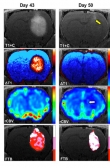

فریب سلول سرطانی با روشی جدید

نتایج تحقیقات پیش بالینی نشان می‌دهد که ترکیب آهن مانند برای درمان بیماران مبتلا به گلیوبلاستوما، یک سرطان تهاجمی مغز، نویدبخش است.